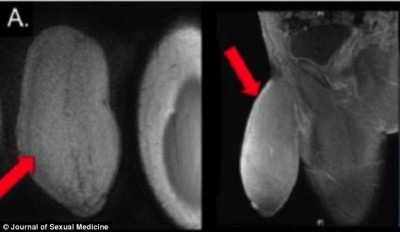

Jovem de 17 anos é submetido à primeira cirurgia para diminuir pênis do mundo

Um adolescente de 17 anos chamou atenção na Internet e no mundo médico nos últimos dias.Ler mais